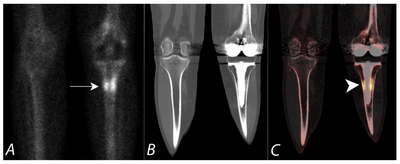

Пухлини кісток

КТ може виявити пухлини кісток, створюючи детальні зображення кісток. Зображення з високою роздільною здатністю, отримані за допомогою КТ, можуть допомогти лікарям визначити місце розташування, розмір і форму пухлини.